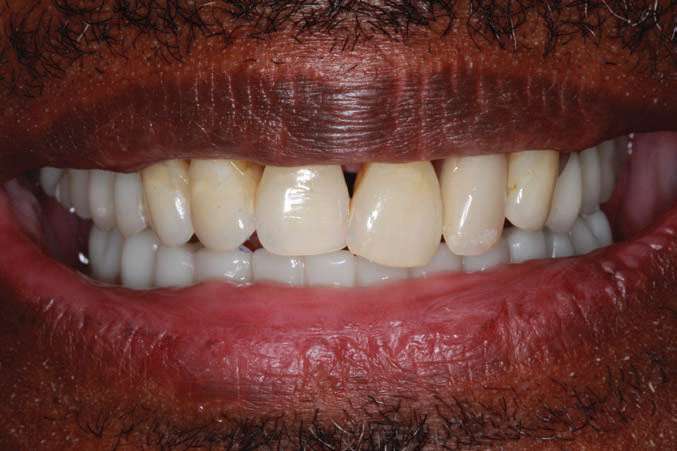

The final monolithic zirconia restoration was fabricated based on the same digital design as the approved PMMA provisional, allowing the patient and his wife easy access for all cleaning implements. The patient had little food impaction and was comfortable with his border movements and ability to really cut and chew his food.

The completed BruxZir Full-Arch Implant Prosthesis is the culmination of great communication with the dental lab team. The final prosthetic result ensured that the patient would not only enjoy his new bridge but would also be able to clean and maintain it with one hand (Figure 20). The relaxed smile view and postoperative Panorex (Figures 21 and 22) shows appropriate lip and tooth display and was a vast improvement over his removable lower denture. The full-face, postoperative photo (Figure 23) of the pleased patient demonstrates that the dictates of aesthetic rehabilitation were met.